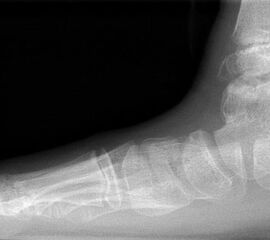

Die beiden häufigsten primären malignen Knochentumoren überhaupt, das Osteosarkom und Chondrosarkom, finden sich neben dem Ewing-Sarkom auch im Bereich des Fußes am häufigsten. Diese Tumoren können sich klinisch wie auch bildgebend sehr variabel darstellen, was die hohe Anzahl von Fehldiagnosen und verzögerten Diagnosestellungen erklären kann 25. Osteosarkome treten im Bereich des Fußes im Vergleich zu den typischen Lokalisationen (kniegelenksnah) durchschnittlich ca. 10 Jahre später auf (Abb. 15). Der Calcaneus ist die bevorzugte Lokalisation für Osteosarkome des Fußskeletts und ein Großteil dieser Tumoren ist schlecht differenziert (G3) 46. Das Verteilungsmuster des Ewing-Sarkoms ist noch heterogener. In einer Nachuntersuchung von 1997 zeigten sich 6 von 16 Ewing-Sarkomen im Bereich der Metatarsalia, 4 in den Phalangen, 3 im Calcaneus und jeweils eines im Talus und eines im Os navikulare 47. Das durchschnittliche Patientenalter unterscheidet sich nicht von den herkömmlichen Lokalisationen. Auffällig ist jedoch die erhebliche Diagnoseverzögerung. So vergehen bei einem Ewing-Sarkom-Befall des Fußes durchschnittlich 14 Monate von Beginn der Symptome bis zur korrekten Diagnosestellung, bei Lokalisation im Rückfuß sind es gar 22 Monate (Abb. 28). Die Therapie des Ewing- und Osteosarkoms des Fußes unterschei­det sich grundsätzlich nicht von der etablierten Behandlungsstrategie dieser Tumoren und umfasst in der Regel die neo-adjuvante Chemotherapie, weite Tumorresektion und anschließende adjuvante Chemotherapie. Die Strahlentherapie besitzt in der Behandlung des Ewing-Sarkoms unverändert einen hohen Stellenwert. Ewingsarkome sind definitions­gemäß stets schlecht differenziert (G3 bzw. G4), also hoch maligne. Das operative Vorgehen ist dieser Tatsache anzupassen.

Metastasen finden sich in den distalen Abschnitten der Extremitäten deutlich seltener als in den proximalen (Abb.29 und 30). Am Fuß sind Metastasen somit vergleichsweise selten anzutreffen (<1%). Lungenkarzinome stellen hierbei den häufigsten Primärtumor dar 48 (Abb.31).